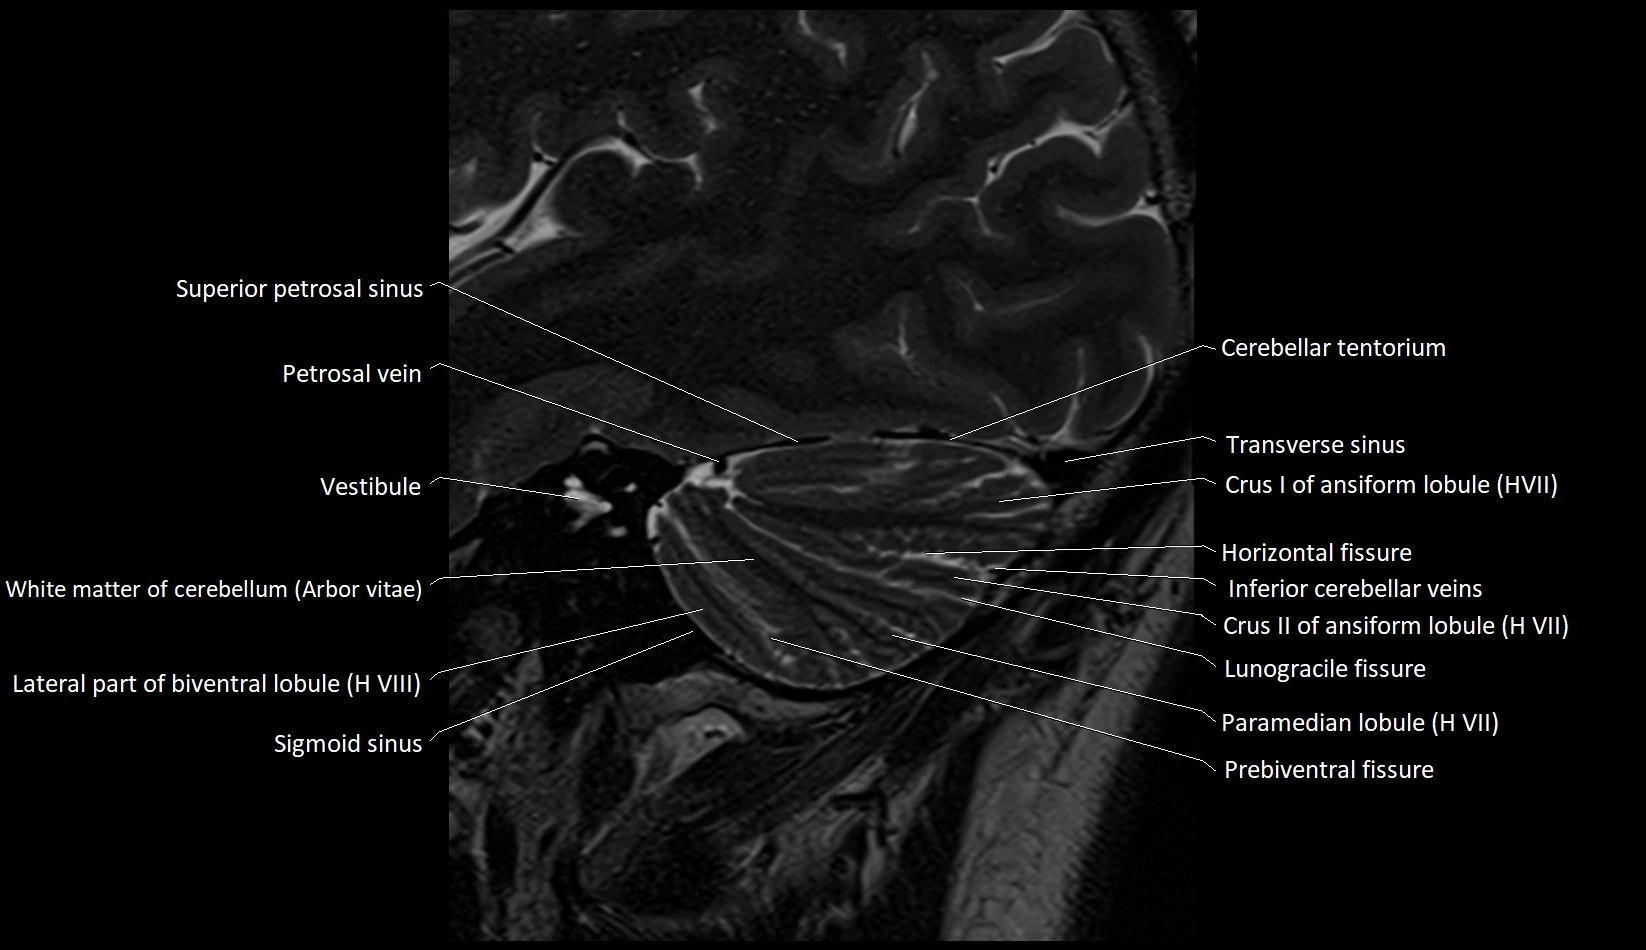

MRI images